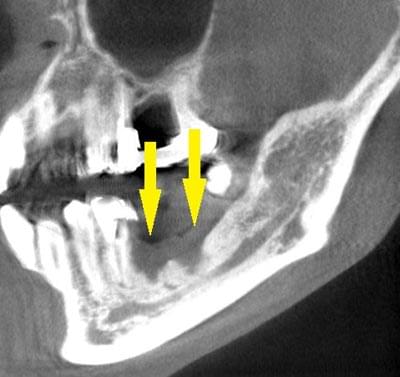

写真のように、CTで見ると、骨吸収の様子が良く分かり、下顎骨の中を通る神経近くまで骨がありませんでした。

さらに、CTで、別な方向から見ると、黄色矢印のように骨が吸収されていて、緑色矢印で示される神経の通る管に迫り、インプラントが埋入できるような骨量はありませんでした。